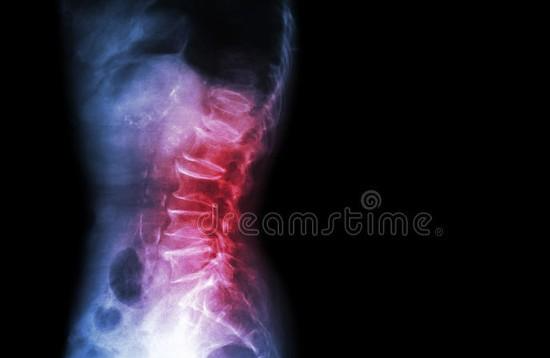

腰间盘突出:疼痛源头腰间盘突出是一种常见的腰痛原因,但首先,让我们来理解一下腰椎和椎间盘是什么。

腰椎,简单来说,就是你腰部的骨骼结构,它们在支撑你的上半身重量、保护脊髓的过程中发挥着关键作用。与腰椎相邻的是椎间盘,它们是软骨样的垫片,位于相邻的腰椎骨之间,起到减震和缓冲的作用。

腰间盘突出就是指这些椎间盘的一部分突出或移位,可能压迫到周围的神经,导致疼痛。这种疼痛通常表现为腰部剧痛,有时还伴随着下肢的刺痛或麻木感。腰间盘突出的主要原因之一是年龄,随着年龄的增长,椎间盘会逐渐失去水分,变得更容易受损。

理解了这些基本概念后,我们可以明白腰间盘突出的本质,它是由于这些软骨样垫片的异常变化引发的疼痛。然而,是否可以通过按摩来“按回去”腰间盘突出呢?